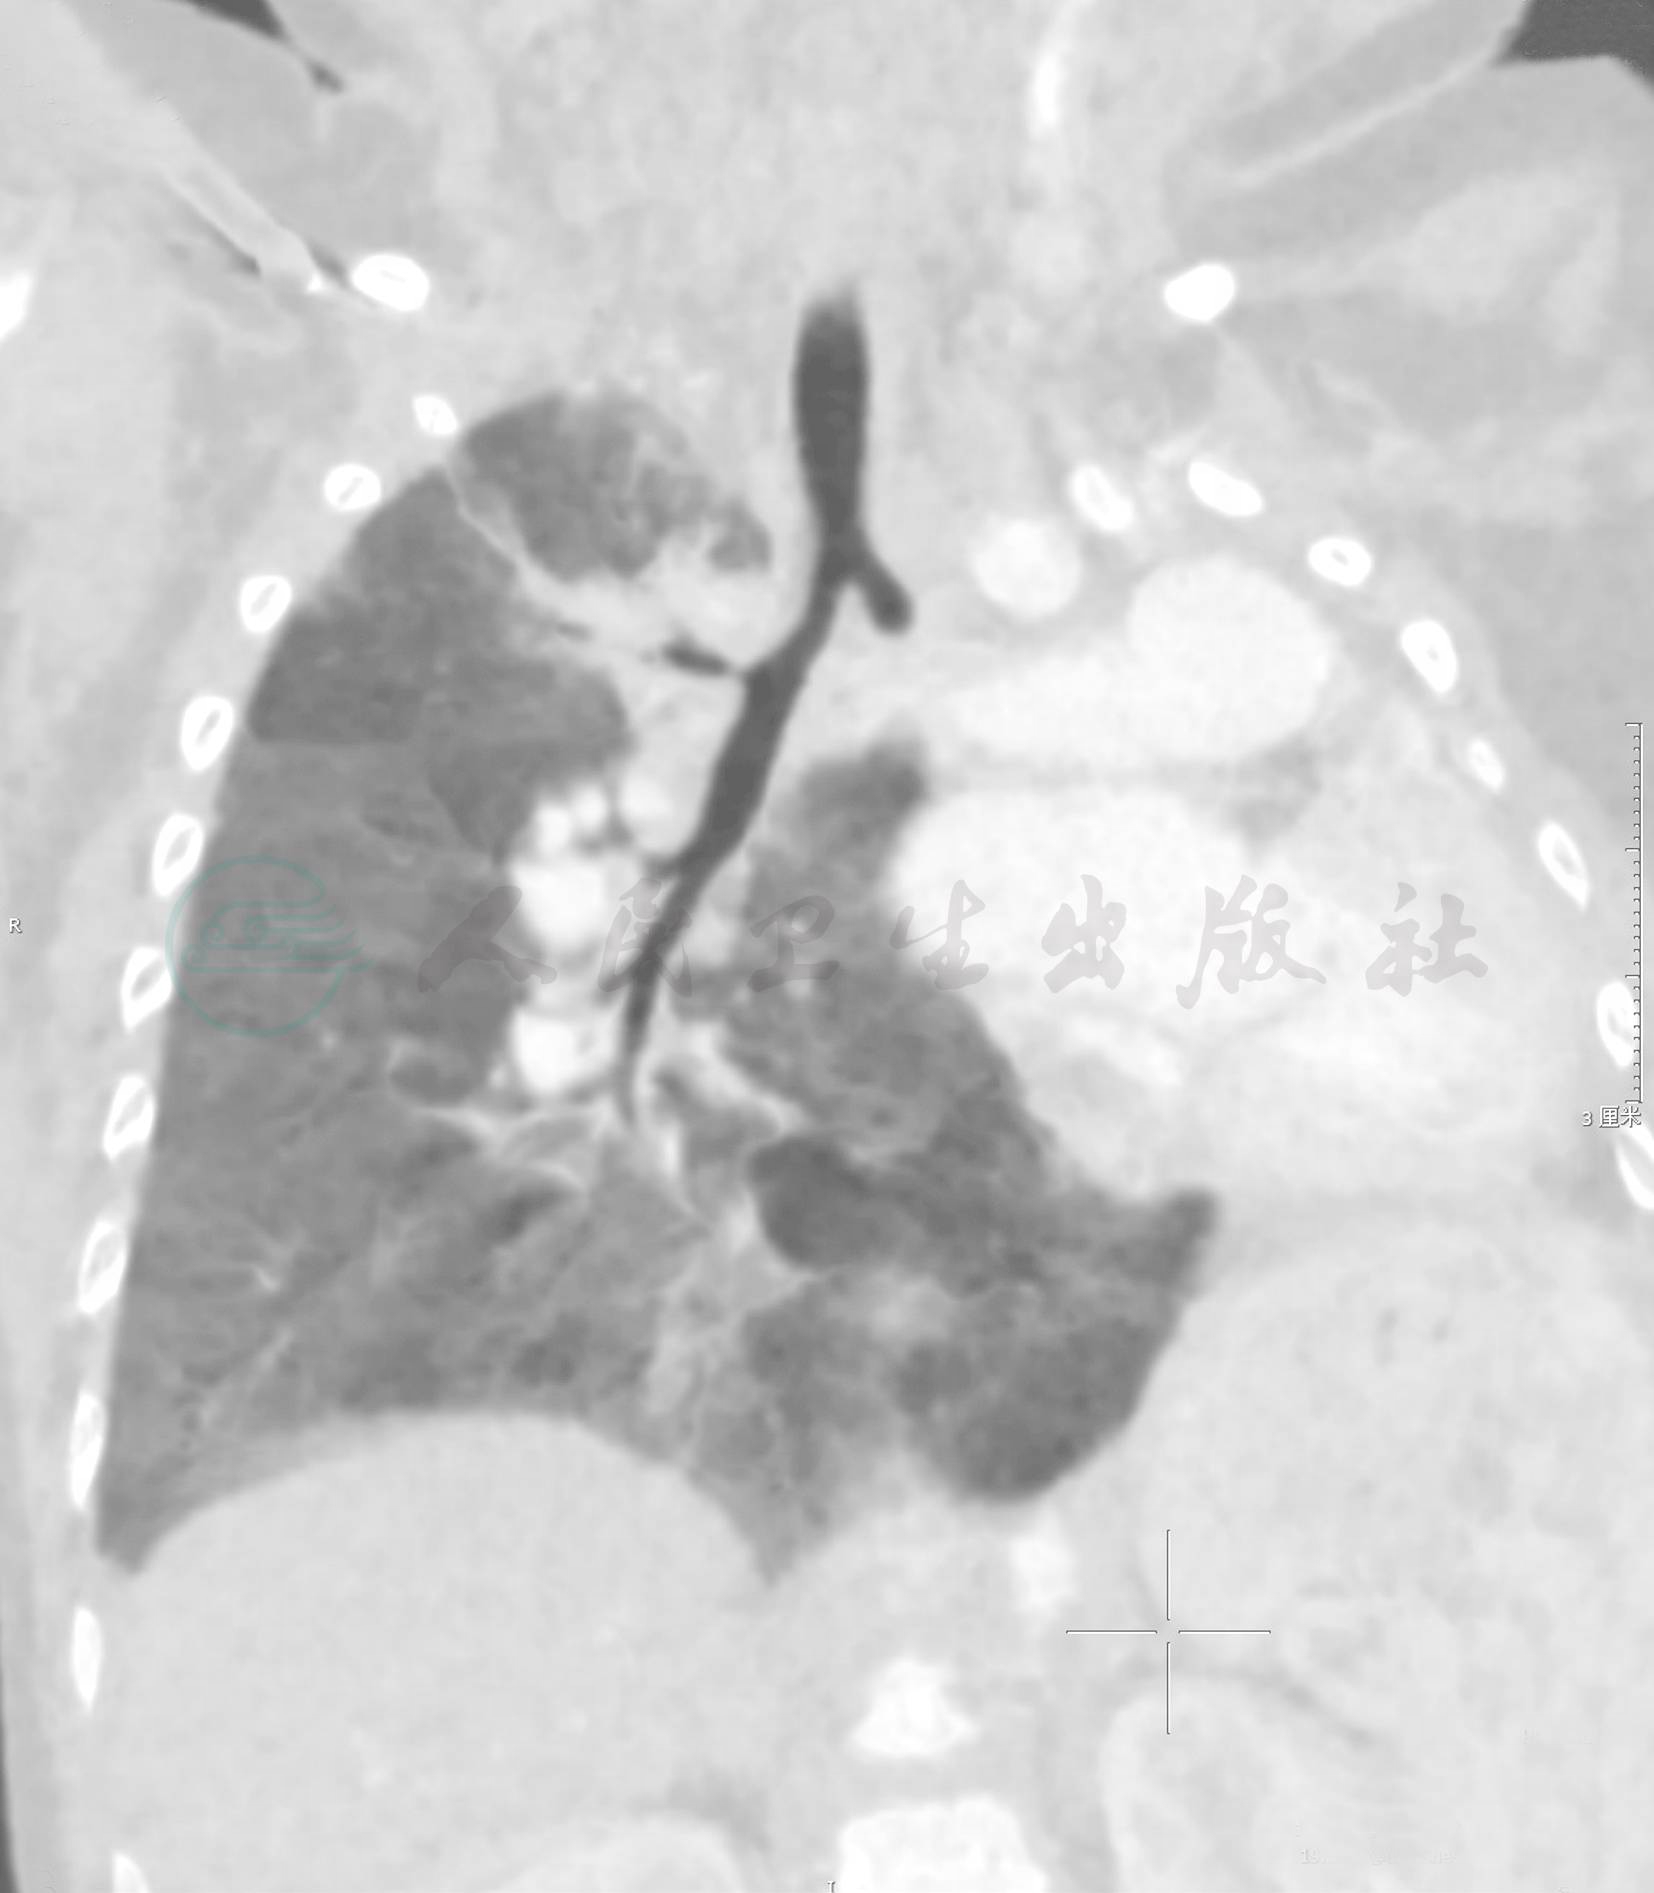

图2肺未发育型

患儿男,7个月,嗓子“呼噜”23天。左侧胸廓较对侧小,未见含气左肺组织影,左主支气管起始处可见,远端呈盲端

引自:实用小儿呼吸病学(第2版).第2版.ISBN:978-7-117-29425-6.主编: